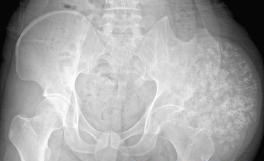

1.X线检查:软骨肉瘤X线表现为一密度减低的阴影,病灶中有斑点状或块状钙化点。

3.辅助检查:软骨肉瘤X线表现为一密度减低的阴影,病灶中有斑点状或块状钙化点。放射性核素扫描可用于检查中央型及周缘型软骨肉瘤。CT检查在中央型与周缘型软骨肉瘤中均有用途,可以了解肿瘤在骨内及软组织中的范围。在周缘型软骨肉瘤的帽盖的厚度,可以帮助分析原来存在的骨软骨瘤有无恶变。病理检查:是软骨肉瘤诊断的金标准。